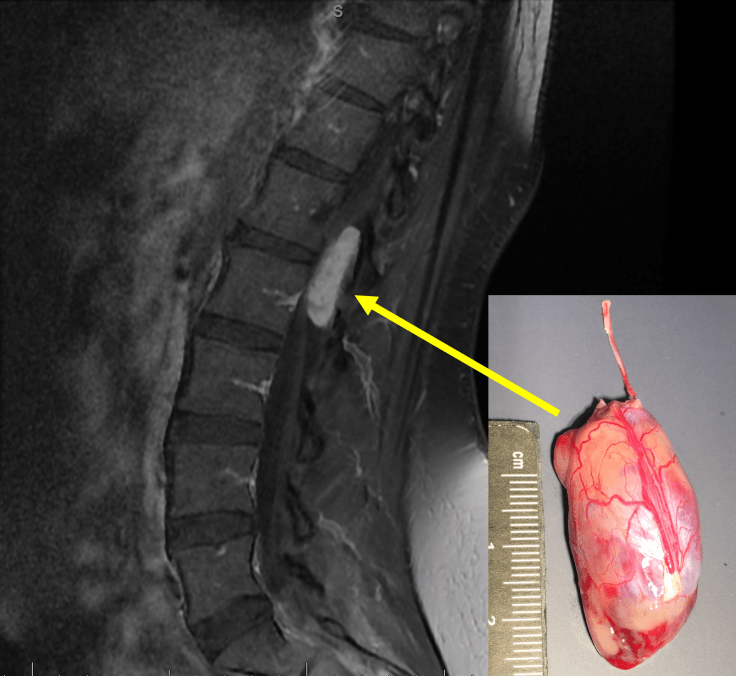

Myxopapillary ependymoma arises in the lumbar region of the spinal cord and typically produces symptoms associated with impingement of the spinal nerve roots of the cauda equina. It usually appears as an oval or sausage-shaped contrast-enhancing mass, like the one pictured in this MRI image (sagittal post-contrast T1 Fat-sat). The myxopapillary ependymoma in the inset photograph represents a gross surgical specimen received from a patient who had undergone optimal therapy: en bloc or gross total excision, in which the entire tumor is removed from the thecal sac without disturbance of the external capsule. Partial or incomplete tumor resection may result in spillage of tumor cells into the thecal sac and, consequently, these patients often experience local recurrence.